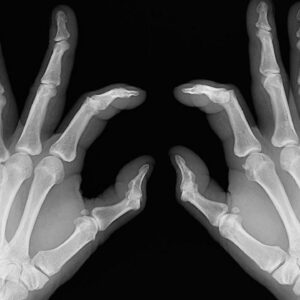

Early signs of rheumatoid arthritis and how to catch them

Rheumatoid arthritis causes chronic inflammation of joints, which results in joint pains, inflammation and bone deformation. It usually starts slowly with pain in some parts of the body that can come and go in the beginning and then spread within weeks or months. It is better in this day and age to always be aware of your health problems and not to ignore slightest of joint pains.